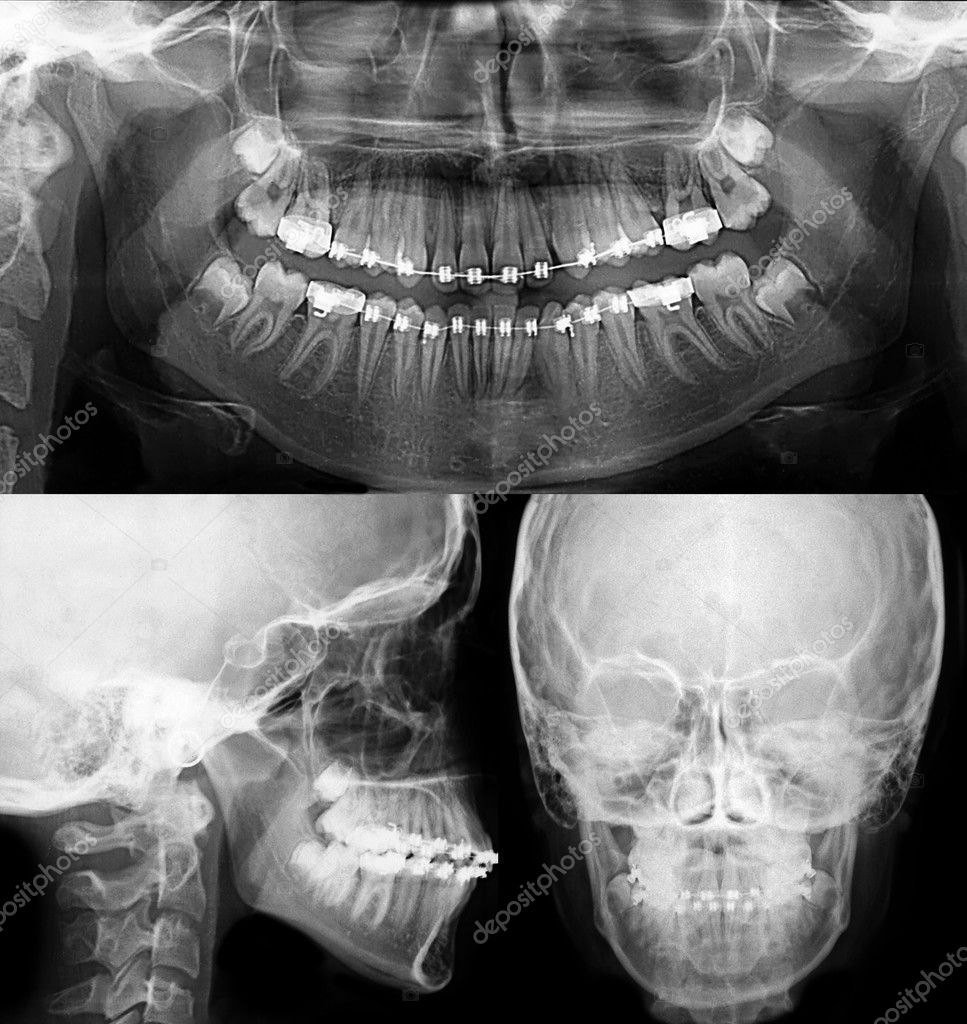

- Chụp phim x-quang: Panorama, cephalometric, CT Conebeam nếu cần

Phân tích phim X – quang chỉnh nha